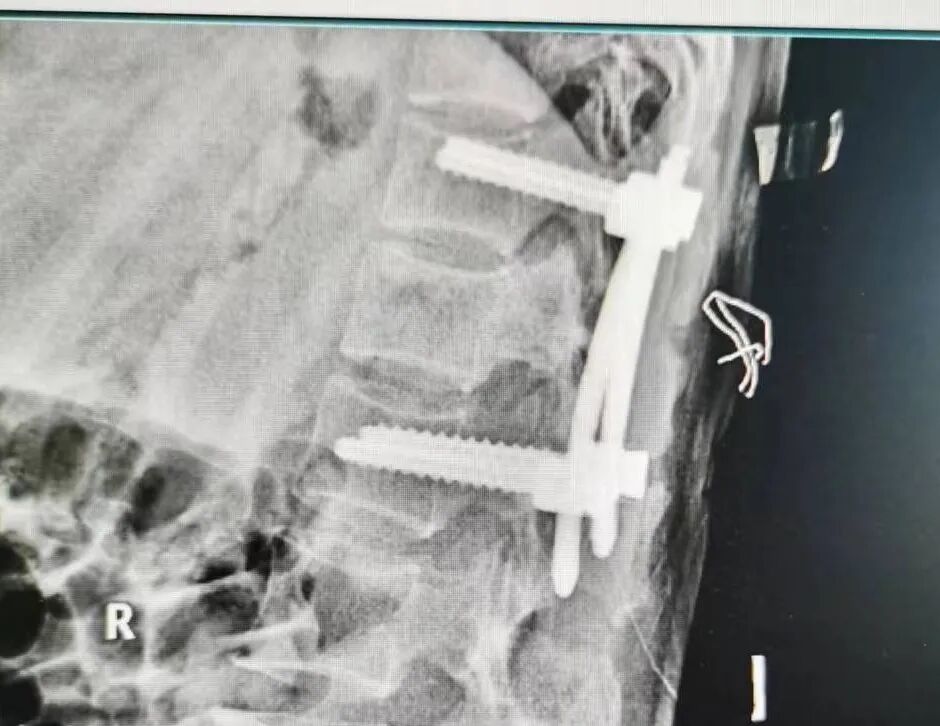

在麻醉科的通力协作下,由陈龙潭医生主刀,张林医生协助,为患者成功实施了微创经皮椎弓根螺钉内固定手术。术中,两位医生紧密配合,熟练运用C臂机透视定位,经皮肤打孔植入钉棒内固定系统,术后骨折复位满意,螺钉固定位置良好,椎体高度恢复满意。

整个手术用时短,出血量少,患者术后安返病房。术后在护理团队的精心护理下,患者顺利康复出院。